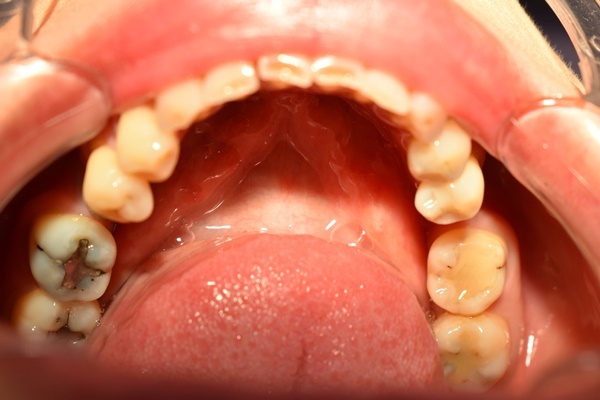

說來慚愧,小弟我年少不學好,國中就跟著叔叔伯伯們在工地吃著檳榔抽著菸,日復一日造就我的口腔髒到無法無天…後來轉行當廚師,雖然有戒掉檳榔,但菸癮依舊在,就在某次試吃新菜色,嚼著嚼著就把牙齒嚼斷了。

現在也才二十有八,年紀還沒三開頭就缺了一顆牙,還好死不死就缺在前面那排,張口微笑就可以看到,被自己員工笑了一陣子,害得我也沒什麼尊嚴。也跟朋友聊了一陣子,到處在台中牙醫、中部牙醫、某某某牙醫等等字眼來回往返,還到處去各家診所裡面諮詢,但每次評估下來都覺得好像不是那麼理想,經濟考量、植牙方式種種我都不是很滿意,才在半年前經過幾個大雅在地朋友介紹這家中部植牙的新全美牙醫,說道嘴角都泡,這裡好那裡好的,也因為自己已經到處跑了這麼多家診所,就不疑有他直接線上掛號諮詢植牙手術。

然後就掛到陳怡睿醫師植牙諮詢門診,問下來這個陳醫師植牙方式好像比較符合我想做的微創植牙需求。我這7個多月植牙經歷最一開始就是,先掛第一次門診,就去到現場給陳醫師做植牙諮詢,接著第二次回診會帶你做斷層掃描和洗牙,一連串心理建設後,才會開始微創植牙手術,我在台中牙醫諮詢也不下6、7間,老實說我有一度覺得我們台中牙醫是不是都挺沒耐心的?有點急著講然後急著要你直接確定,講到心情不是很好,但來台中大雅新全美牙醫就有感受到滿滿的愛哈哈,一連串都蠻貼心仔細,也不會說你都來諮詢了趕快確定,不會!醫師還會說你好好考慮一下,這邊先幫你評估適不適合而已,可以回家好好想想,就因為這麼簡單又阿沙力,我也很乾脆就決定在這裡做微創植牙,心情舒爽。

再來第三次回診檢查傷口,這天比較緊張,因為沒問題就可以靜待3到6個月再等下次回診就可以咬模做假牙。不過那天去之前我牙齦突然有點小流血,很怕要再多等兩三個月,一直到診間都有點緊張…好禮家在,陳醫師說這個不是傷口那邊出血,還是可以咬模,也讓醫師幫我清理很久,有點小不好意思哈哈。

這微創植牙手術過程有點繁複,但是能感受陳醫師植牙手術過程帶給我的細心感受,有種暴徒找到良心,惡疾找到良醫的違和感,簡直是天賜良緣…

現在是還在戴臨時假牙,但陳醫師說植牙只剩這幾次回診了,要堅持下去,好好咬合之後就可以用正式假牙,在咬合完全之後,就可以再次回診然後黏住牙齒,就跟全新的一樣,心裡很是彭湃,真的…